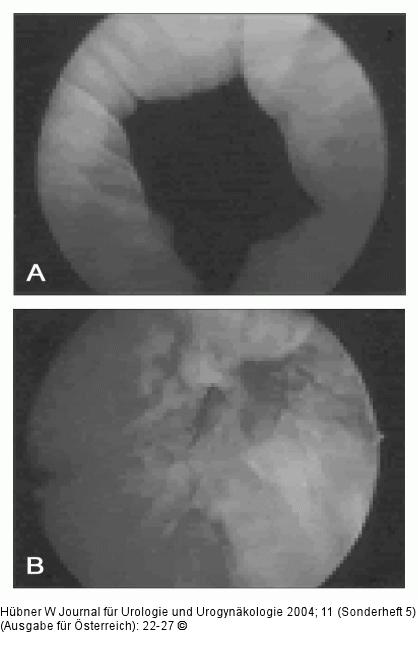

Abbildung 1a-b: Bulking agents "Bulking agents". A: Offener Blasenhals vor Injektion; B: Blasenhals nach Injektion von Kollagen. |